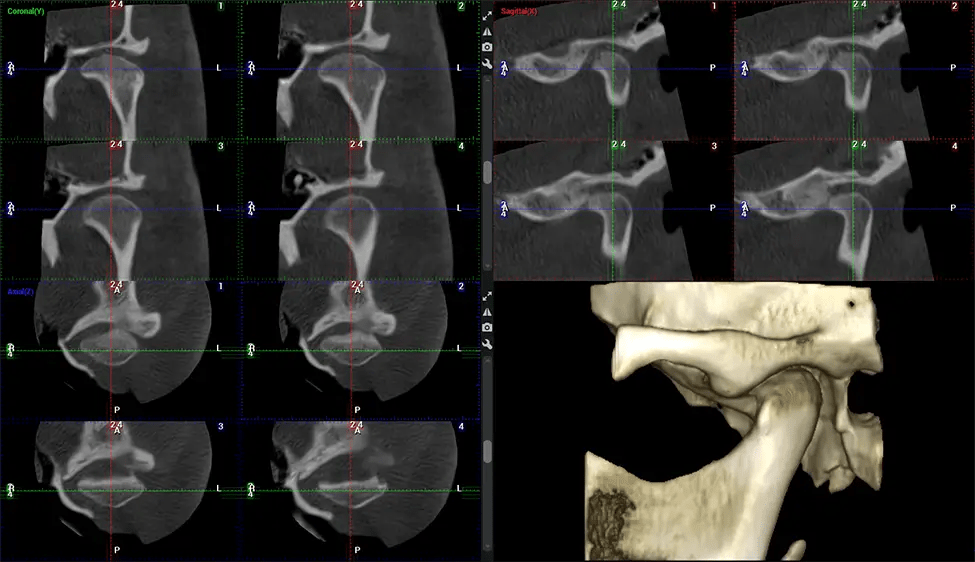

The patient is first positioned in the CBCT scanner, which typically consists of a rotating arm that houses the X-ray source and a detector. The patient’s head is immobilized to ensure accurate image capture. The X-ray source and detector rotate around the patient’s head, capturing various X-ray images from multiple angles. As the X-ray source rotates, it emits the cone-shaped X-ray beam towards the detector. The detector captures the X-ray images, which are then processed by the CBCT software.

After the scanning process, the captured X-ray images are processed by the CBCT software, which applies algorithms to reconstruct a detailed 3D image of the scanned area. The software compiles these individual X-ray images and creates a digital 3D representation of the patient’s anatomy. The reconstructed 3D CBCT image can be viewed and analyzed by the dentist or radiologist. This image can be manipulated, rotated, and zoomed in or out to examine specific structures and evaluate the patient’s condition.

Planmeca Viso G7 CBCT ( Cone Beam CT Scan ) is designed to surpass the demands of industry leaders, specialists, and large institutions. It’s has a large ø25×30 cm sensor with four built-in cameras. It can capture unlimited volume sizes from a ø3×3 cm to a ø30x30cm volume capturing the skullcap through C7 on the cervical spine. The Planmeca Viso G7 offers the industry’s largest single volume scan of ø30×19 cm. It’s poised to handle advanced imaging modalities such as Planmeca ProFace® and Planmeca 4D™ Jaw Motion technology. The occipital head support allows an unimpeded view of facial tissue.